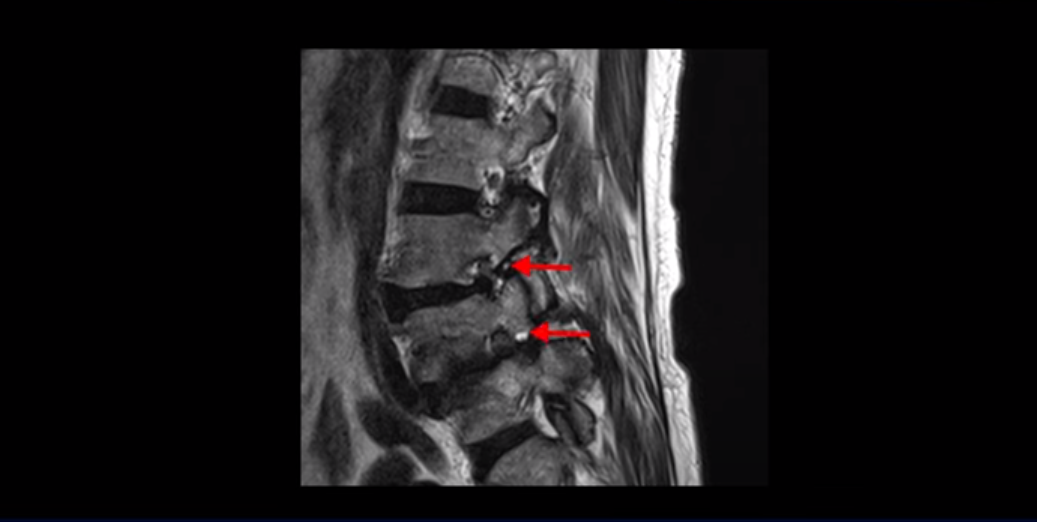

실제 저희 치료후기에 나오는 환자분들의 사례를 들어 설명해드리겠습니다. 이분은 전방전위가 2단계로 매우 심하고,

신경 구멍도 두 마디가 좁아져 있습니다.

전방전위와 협착이 다 심하니까 대학병원에서 나사 6개를 박는 유합술을 권유 받으셨는데요. 그런데 이분이 처음 아프게 된 건 작년 10월인데, 이분이 만약 아프기 전인 작년 초에 MRI를 찍었다면 지금의 MRI와 많이 다를까요? 아닙니다. 거의 차이가 없을 겁니다. 이미 척추 뼈는 많이 밀려나가 있고 신경 구멍은 똑같이 좁아진 상태였을 겁니다. 그 상태로도 전혀 안 아프게 아주 오랫동안 사신 겁니다. 그러다가 작년 10월에 무리한 일과 운동 때문에 허리 근육에 문제가 생기면서 신경이 눌리기 시작한 겁니다. 만일 아프지 않을 때 MRI를 찍고 척추 뼈가 밀려나가고 신경이 눌렸으니까 나사 박는 수술을 하자고 하면, 수술을 받을 사람이 있을까요?